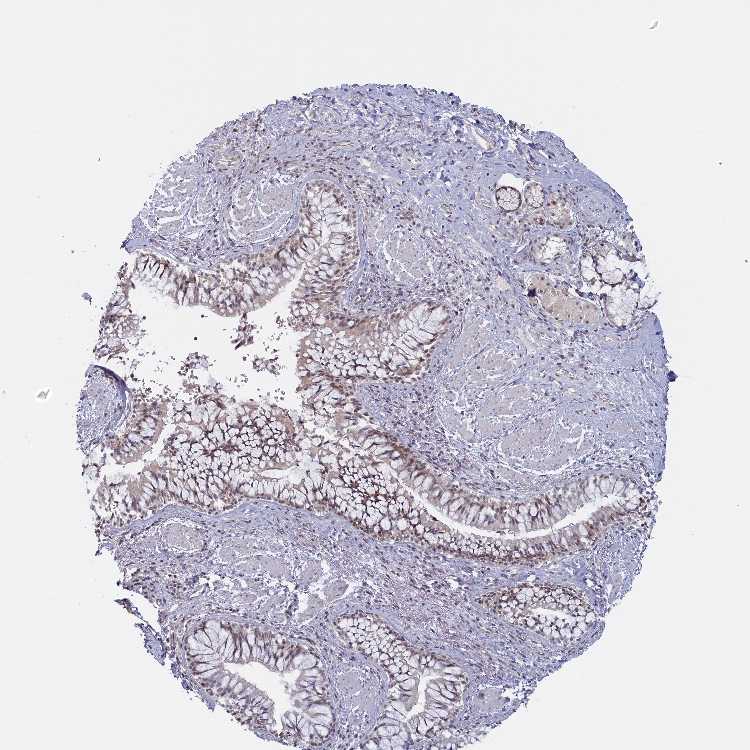

SOFT TISSUE 1 - Antibody stainingi

Antibody staining in the annotated cell types in the current human tissue is reported as not detected, low, medium, or high, based on conventional immunohistochemistry profiling in selected tissues. This score is based on the combination of the staining intensity and fraction of stained cells.

Each image is clickable and will lead to virtual microscopy that enables deeper exploration of all samples and also displays staining intensity scores, fraction scores and subcellular localization as well as patient and tissue information for each sample.

Antibody HPA040914Antibody HPA041187

Chondrocytes LowNot detected

Fibroblasts LowNot detected

SOFT TISSUE 2 - Antibody stainingi

Fibroblasts Not detectedNot detected

Peripheral nerve Not detectedNot detected